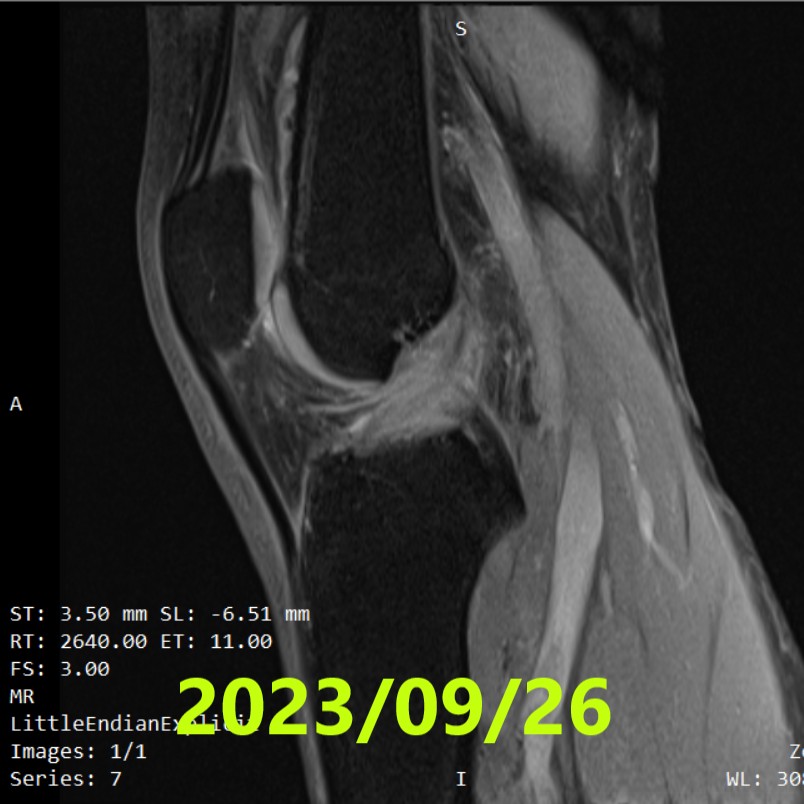

第二次 MRI(約 3 個月後)

- 拍攝日期:2023年8月下旬(治療開始 3 個月後)

- 所見:可確認韌帶的自然癒合(連續性),但觀察到韌帶有「鬆弛」現象

- 臨床所見:Lachman 測試陰性

- 方針變更:為提高韌帶穩定性,強烈要求佩戴護具,並物理性限制 0〜30° 的伸展運動。